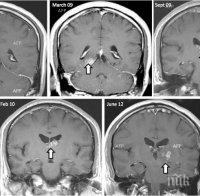

При преглед на белите и черния дроб, надбъбречните жлези и лимфните възли лекарите намерили множество злокачествени образувания. Специалистите били смутени от факта, че раковите клетки се оказали твърде малки.

Понататъшните изследвания и ДНК анализи показали, че болните клетки са се предали на човека от тения.

Уникалният пациент починал след 72 часа, след като лекарите намерили туморите в организма му. Към момента няма открит начин за лечение на този тип заболяване.